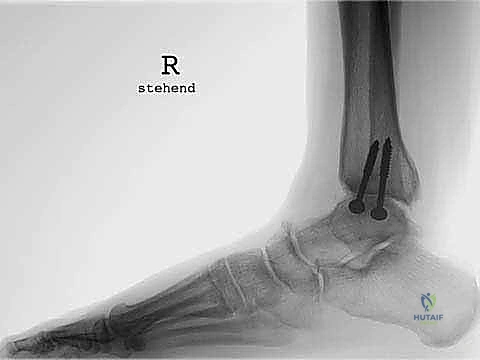

* التصوير الشعاعي المتقدم: صور أشعة سينية (X-rays) في وضعية الوقوف (تحميل الوزن) لتقييم المحور الميكانيكي للساق والقدم.

* الأشعة المقطعية (CT Scan): للحصول على رؤية ثلاثية الأبعاد للعظام، تقييم حجم التكيسات العظمية (إن وجدت)، والتخطيط الدقيق لحجم المكونات المعدنية.

* تقييم التوازن: التأكد من عدم وجود تشوهات في القدم (مثل القدم المسطحة الشديدة أو التقوس) التي قد تؤثر على عمر المفصل الصناعي. إذا وجدت هذه التشوهات، قد يقرر الدكتور هطيف إصلاحها جراحياً في نفس الوقت لضمان بيئة ميكانيكية مثالية للمفصل الجديد.